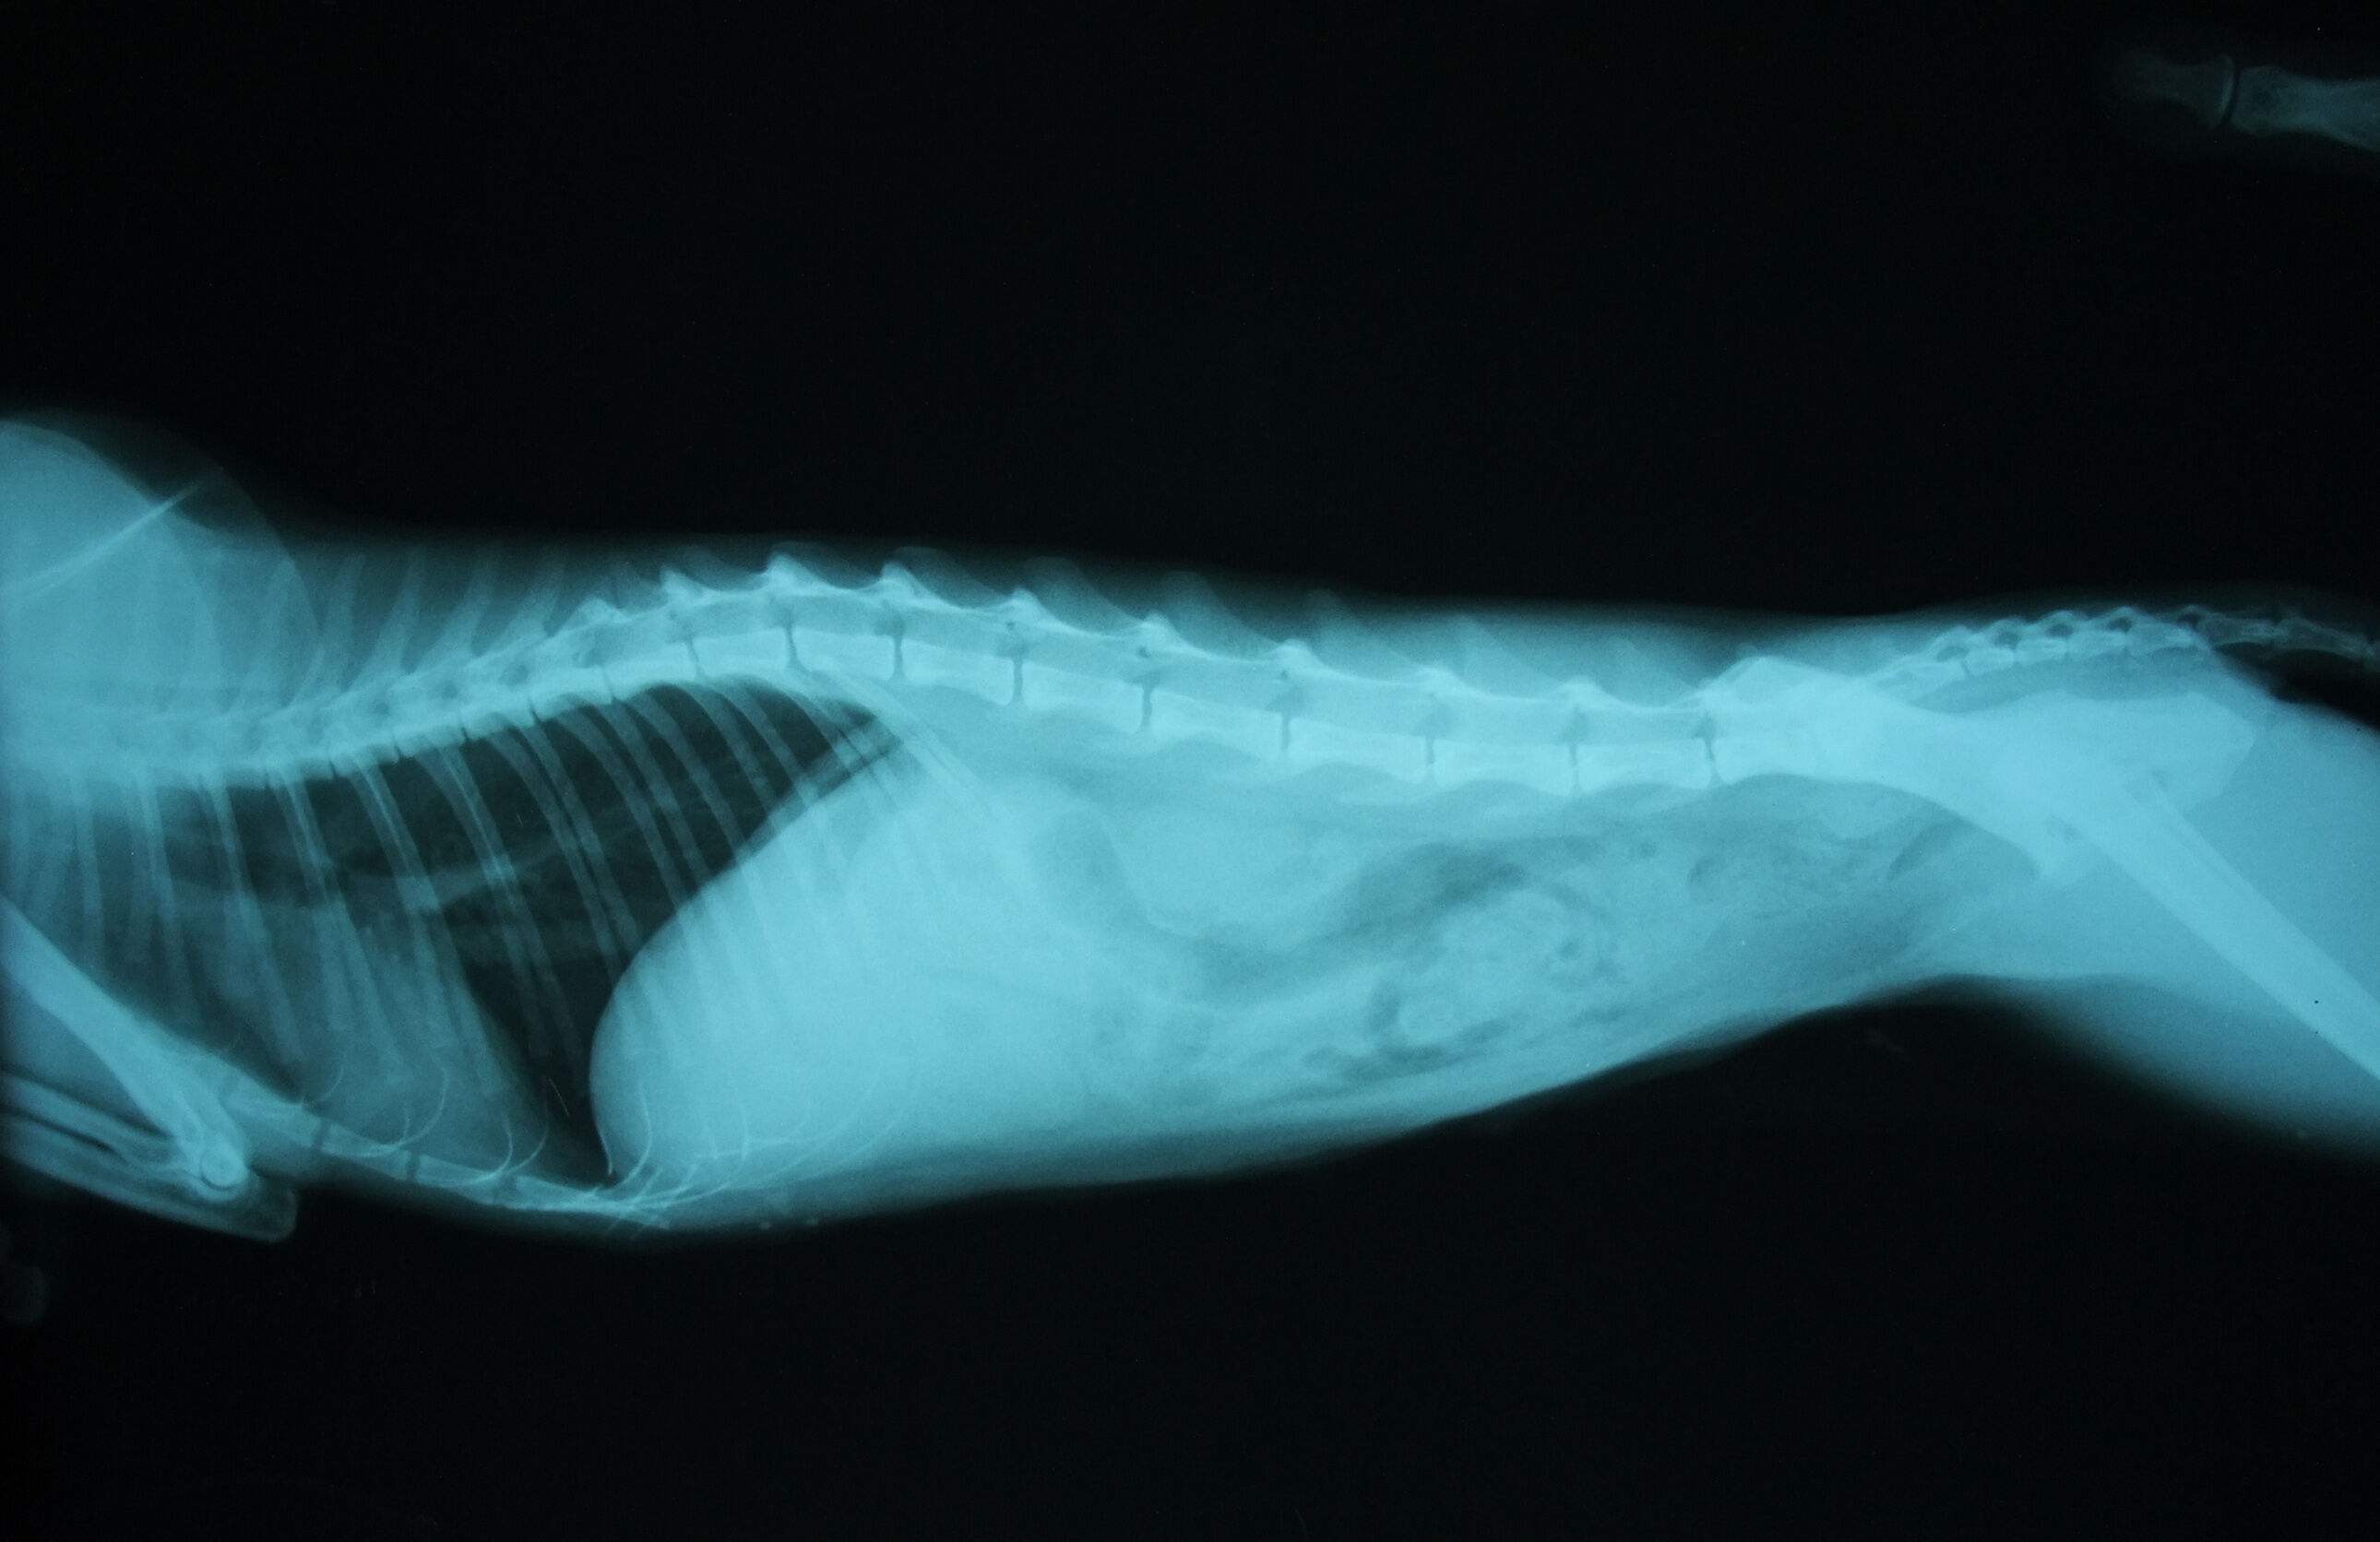

幾天後,腎指數有稍微的下降,但還是高的驚人,所以醫生拍了X光確認,我們看到,一顆腎臟已萎縮,一顆則異常的腫大。醫生說,因萎縮的腎臟已失去功能,所以造成另一顆腎臟過度使用,但不代表它的運作功能是正常的。